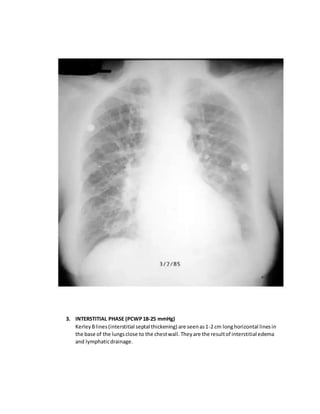

3. INTERSTITIAL PHASE (PCWP18-25 mmHg)

KerleyBlines(interstitial septal thickening) are seenas1-2 cm longhorizontal linesin

the base of the lungsclose to the chestwall. They are the resultof interstitial edema

and lymphaticdrainage.

There isalso peribronchialcuffing andperihilarhaze( lossof definitionof vessels).This

occurs whenfluidleaksintothe peribronchovascularinterstitium